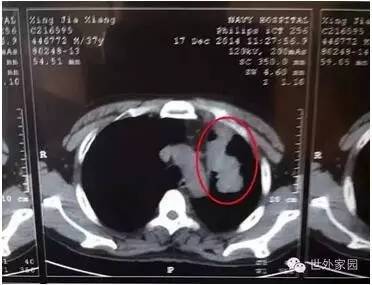

2014年12月17日CT结果是肿瘤大小7.1*3.5cm

历时28天,行程半个中国,跟随法师,跟随养生营,我们完成了生命里的一次完美蜕变。这也是我和妻子结婚十几年以来,单独在一块朝夕相处最长的一次,让我们也领会了幸福人生的真正含义。回到淄博,简单安置了家里和公司的一些事情后,我来到北京复查。其实,内心并没有抱着那么高的奢望,肿瘤能够缩小一部分,我也是可以接受的。师父所讲“病来如抽丝,病去如山倒”的理念,我还是将信将疑的。当三天的检查结束,所有的数据对比凑齐,大夫和护士均目瞪口呆——7.1*3.5CM的恶性肺腺癌四期肿瘤完全消失,癌胚抗原由原先的47.3下降为11.7,离正常值5只差一点点。除此以外,其余各项指标全部正常!按传统的治疗标准说,这已经算是“基本痊愈”。不到五个月,不吃药,不打针,没手术,没放疗,没化疗,没有接受过任何现代医学的治疗,自然康复,我的同学说:“这是奇迹,用现代医学无法解释!”拿到化验结果,欣喜若狂的我,涅槃重生的我,幸福的心情无以言表!

2015年5月13日复查CT肿瘤消失

肿瘤全部消失。(只剩少许胸腔积液,可以随时吸收掉;陈旧性病变是指曾经得肺结核自愈后留下的疤痕。)